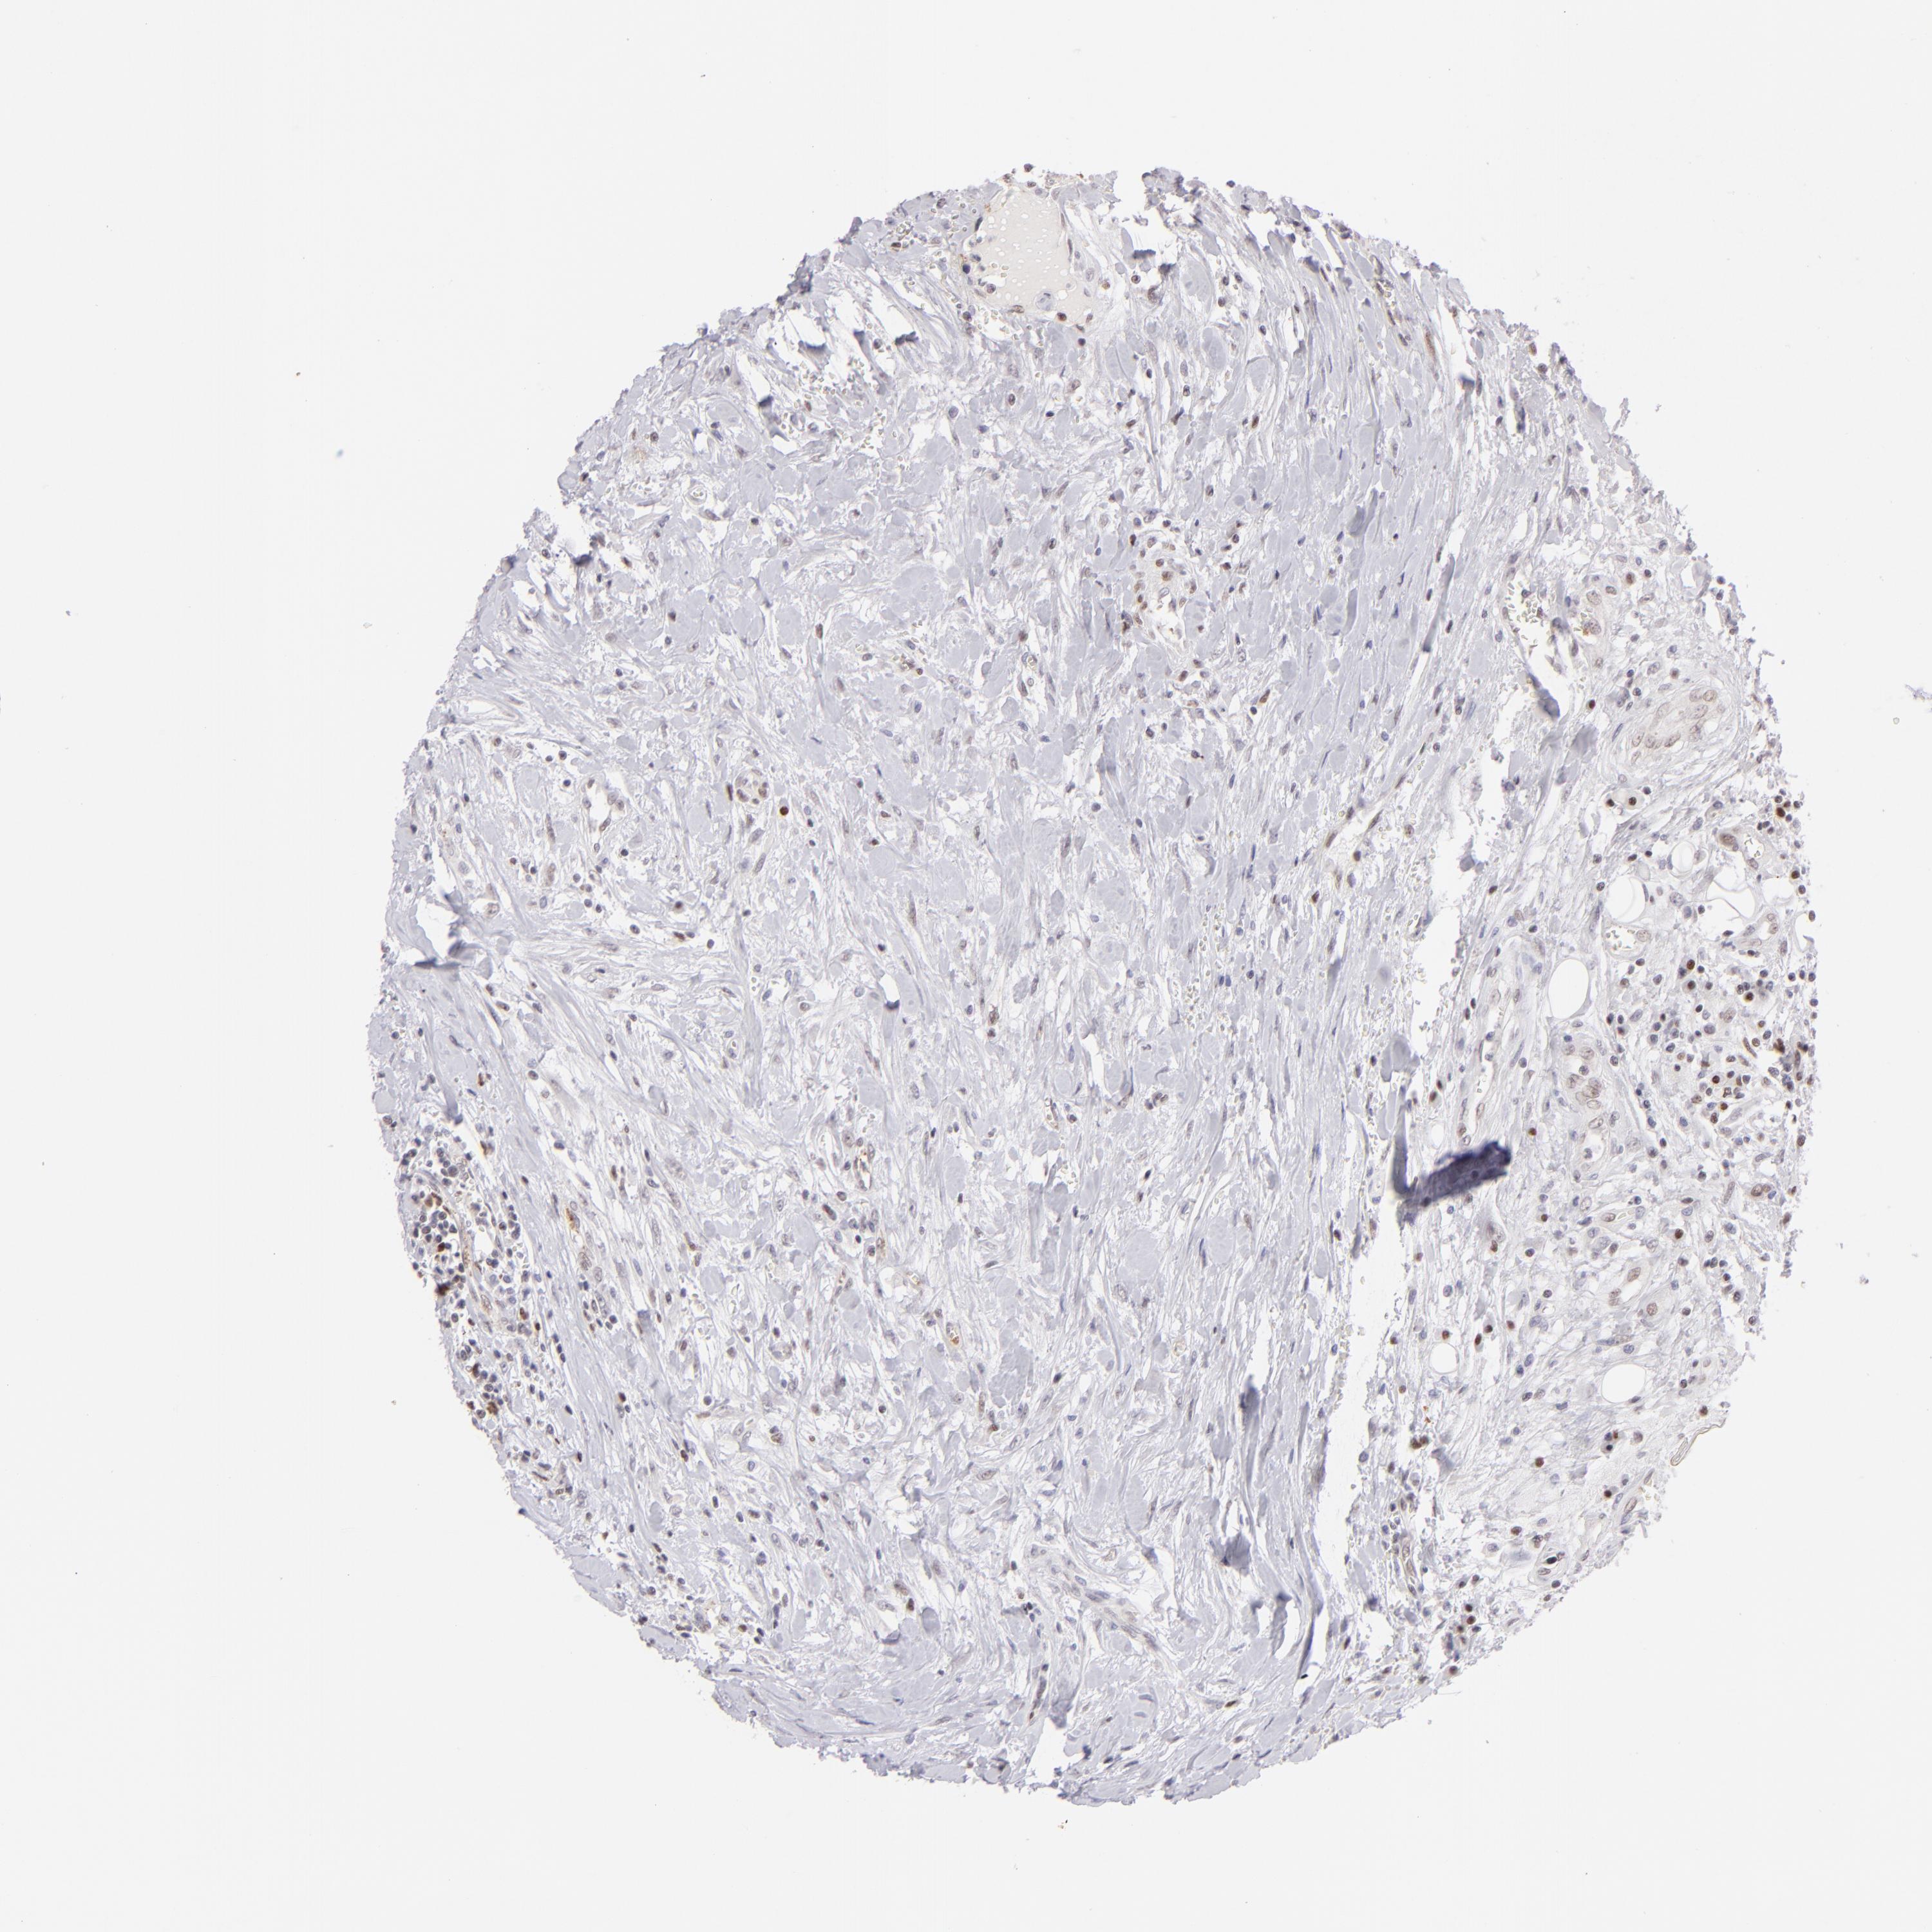

HEAD AND NECK CANCER - Protein expressioni

A mouse-over function shows sample information and annotation data. Click on an image to view it in a full screen mode. Samples can be filtered based on level of antibody staining by selecting one or several of the following categories: high, medium, low and not detected. The assay and annotation is described here.

Antibody stainingi

Antibody staining in the annotated cell types in the current human tissue is reported as not detected, low, medium, or high, based on conventional immunohistochemistry profiling in selected tissues. This score is based on the combination of the staining intensity and fraction of stained cells.

Each image is clickable and will lead to virtual microscopy that enables deeper exploration of all samples and also displays staining intensity scores, fraction scores and subcellular localization as well as patient and tissue information for each sample.

Antibody CAB002608

Squamous cell carcinoma, NOS

Adenocarcinoma, NOS

Squamous cell carcinoma, metastatic, NOS